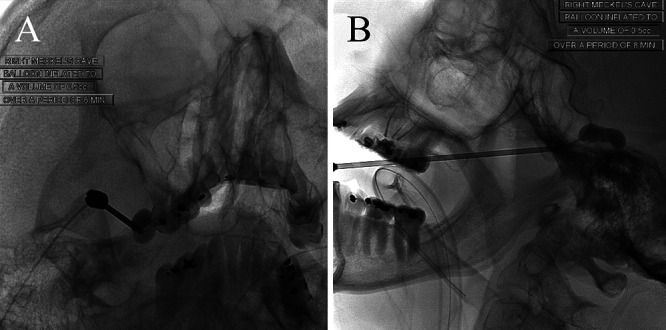

A 64-year-old female initially developed symptoms of bilateral trigeminal neuralgia 40 years prior. In addition, she was status post-right microvascular decompression 23 years prior, balloon rhizotomy 14 years prior, and oxcarbazepine treatment. She described the recurrence of pain on the right as 3–5/10, needle-like, “lightning bolt,” and stabbing. Precipitating events included talking, eating/chewing, brushing her teeth, washing her face, and wind exposure. An increase in medication was not tolerated because of sedative side effects. She underwent a right-sided percutaneous balloon rhizotomy without immediate complication (Fig. 1A and B). She tolerated the procedure well and went home the same day.

FIG. 1.

En fosse and lateral projections of a right-sided balloon rhizotomy with inflation of the balloon up to 0.5 mL for a duration of 8 minutes.